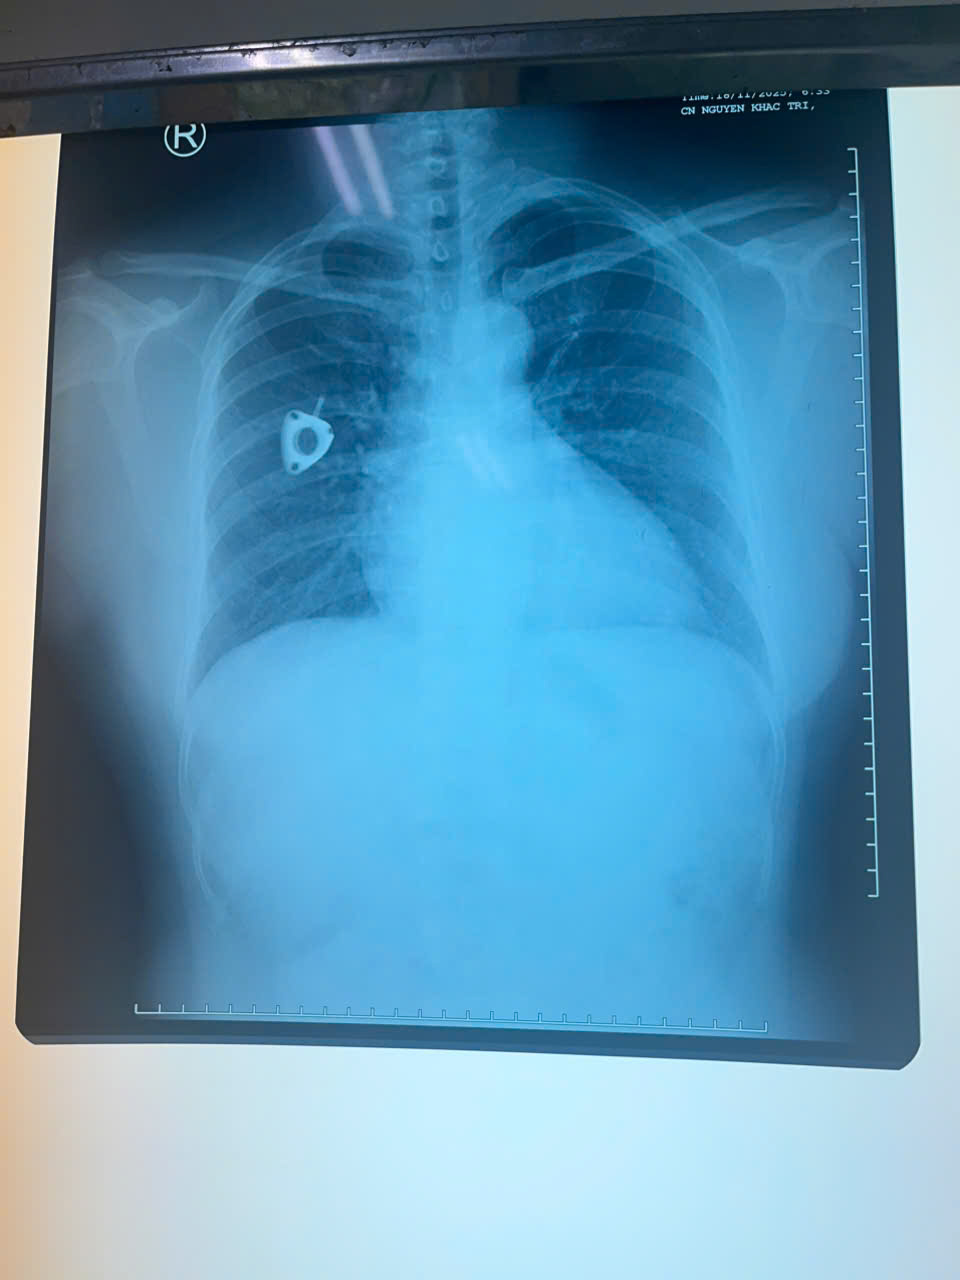

Hình ảnh dị vật chèn ngang động mạch phổi qua phim chụp CT và X-quang

Mới đây, bệnh nhân đi khám tầm soát và chụp CT ngực tại một cơ sở y tế tư nhân thì phát hiện dị vật trong tim, nằm vắt ngang tại vị trí động mạch phổi hai bên. Sau đó, bệnh nhân quay về bệnh viện đã điều trị ung thư trực tràng để tiếp tục thăm khám và được tiến hành chụp X-quang ngực.

Kết quả ghi nhận mất liên tục thân catheter, xác định catheter đã bị đứt. Phần buồng truyền dưới da vẫn còn tại vị trí dưới xương đòn phải, phần đầu còn lại đã di chuyển về tim và nằm trong động mạch phổi.